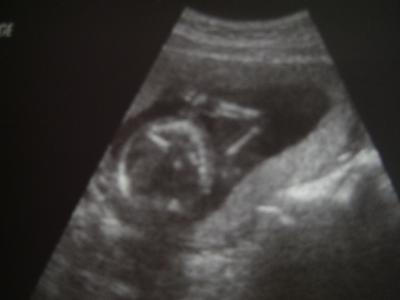

Hi, da bin ich wieder.... ...leider ohne Outing! Aber dem Baby geht es gut. Hat sich heut mal Daumen nuckelnd gezeigt und wurde dabei gleich fotografiert. Vielleicht hab ich in 2 Wochen Glück das Geschlecht zu erfahren. Spätestens zur Feindiaknostik in der 20.Woche wird es sich zeigen müssen. Meine Plazenta hat sich noch nicht verschoben und somit muss ich mich weiter schonen und ich hoffe und bete nicht wieder eine Blutung zu bekommen und das sich das in 2 Wochen zum Ultraschal erledigt hat und alles gut ist. Danke euch für´s Daumen drücken

Bild zu Zurück vom Fa - Forum für August - Mamis

So ein niedliches Bild! Der kleine Arm der zum Kopf führt ist ja schon richtig perfekt!.Freue mich sehr für dich und drücke die Daumen für ein Outing in zwei Wochen!